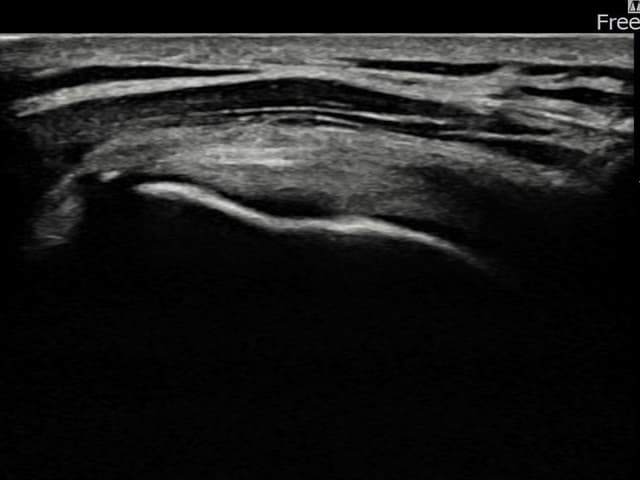

[経過期間: 23.07.31~23.09.27]

[縫縮術] 超音波検査にて左 棘上筋腱 부착부 광범위 部分断裂(13mm × 5mm (腱厚の約65%欠損))を確認。縫縮術施行後、腱の連続性が回復し、日常生活に復帰されました。